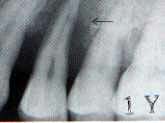

図1.「6 Fop 術前 1987年11月20日 50歳 男性 図2.術後3年。1990年8月16日。歯槽骨吸収程度が比較的

軽度であったため、 有髄歯のまま Fopを施行したが、

強度な知覚過敏と歯周疾患進行により3年後に抜歯。